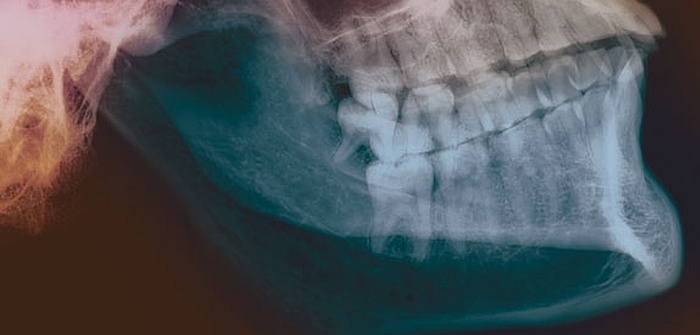

El plasma rico en factores de crecimiento regenera el tejido mandibular

Osteonecrosis mandibular / Foto: The New York Academy of Sciences

La necrosis de los tejidos de la mandíbula por falta de riego sanguíneo "es una patología común en pacientes crónicos que han recibido durante varios años corticosteroides (como asmáticos) y mujeres en tratamiento con bifosfonatos para la menopausia", explica el doctor Javier González Lagunas, presidente de la SECOM. Las pacientes que han recibido bifosfonatos orales durante tres años o intravenosos durante uno o más años, tienen mayor riesgo de sufrir osteonecrosis mandibular, según un documento de consenso elaborado por la SECOM en 2008.

La osteonecrosis mandibular se suele tratar con el reemplazo del tejido dañado por un injerto tras eliminar el tejido necrosado. Sin embargo, el plasma rico en factores de crecimiento ha demostrado que puede ser más eficaz y seguro en muchos casos tanto en la prevención como en el tratamiento de esta enfermedad, comenta por su parte la doctora Torre Iturraspe. Esta tecnología (Endoret® -PRGF®) está basada en la propia sangre del paciente. Tras su centrifugación y fraccionamiento, se obtiene la separación de células sanguíneas por un lado y el plasma y plaquetas por otro. Este plasma contiene una gran concentración de plaquetas, las cuales liberan una gran cantidad de factores de crecimiento provocando distintas señales celulares que aceleran y optimizan la reparación de los tejidos. El año pasado fue reconocido como medicamento de uso humano no industrial por la Agencia Española del Medicamento y Productos Sanitarios.